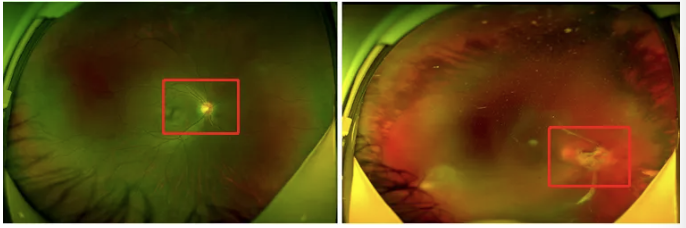

糖尿病性视网膜病变示意图

眼底激光治疗要视具体情况而定,需要1次或多次。如糖尿病性视网膜病变,因病变广泛,需要分成3-4次治疗,每次大约间隔1周时间。其他情况,如视网膜裂孔和周边视网膜变性等,一般需1次治疗即可完成。咨询电话:400-1120-900